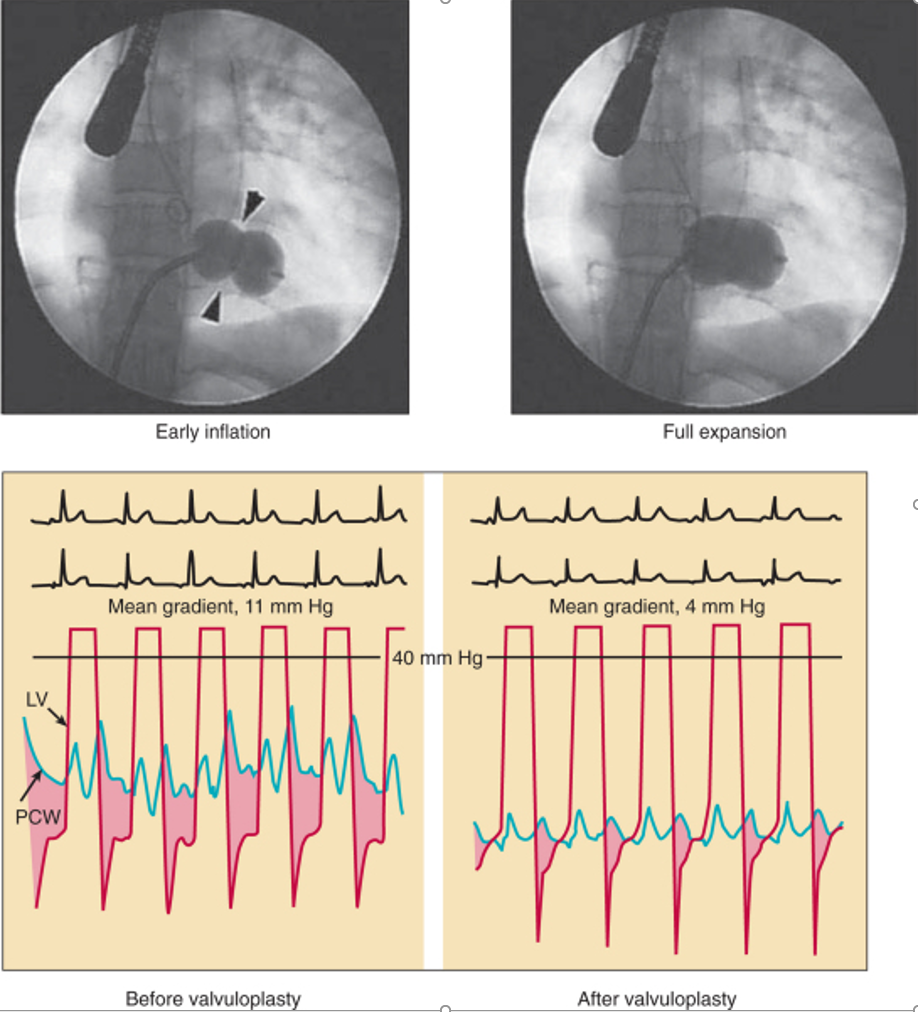

Pressure gradient

- Estimation of the diastolic pressure gradient is derived from the transmitral velocity curve by CWD

- Maximal and mean gradients are calculated by tracing Doppler of the diastolic mitral flow

- Dependent on mitral valve area, heart rate, cardiac output and associated MR

- Has significance following balloon mitral commissurotomy